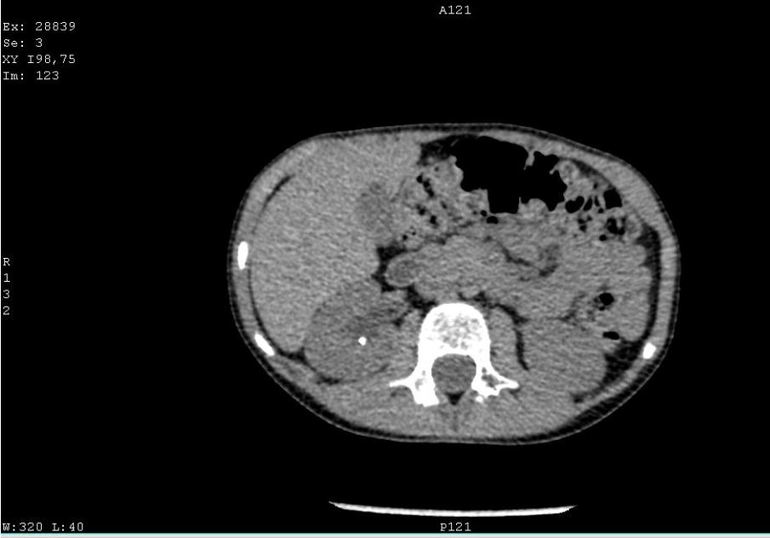

Получилось открыть диск с КТ, вот нашла что-то вроде напоминающее камень.

Хороший конкремент, такой будет видно на УЗИ. При цистоскопии никаких источников гематурии на слизистой не нашли? В чем была выражена макрогематурия, сгустки, равномерное окрашивание?

Здравствуйте. Мне сложно объективно судить о вашей ситуации, поскольку я не видел первоисточников клинической информации. Любые по составу конкременты почки, размерами более 3-4 мм, хорошо видны при УЗИ. Наличие единичного конкремента 3-4 мм, не является обязательной причиной гематурии. Мне кажется в вашей ситуации не все так однозначно.